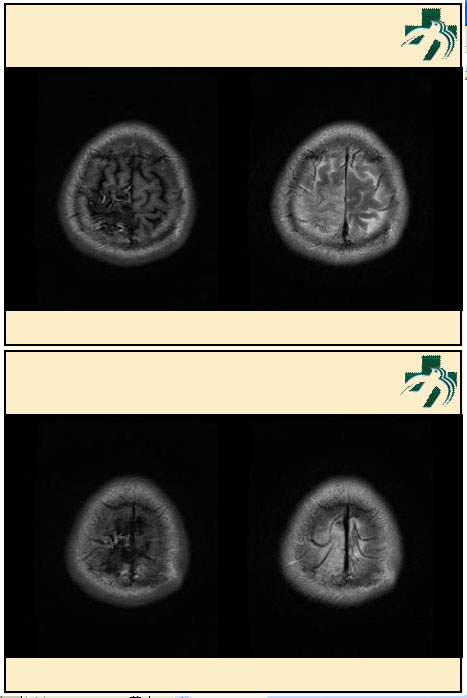

奴卡氏菌感染

第九期三博

读片会

病例之四

北京协和医院 提供

男性,22岁。自觉虫咬后皮疹、肢体麻木4月